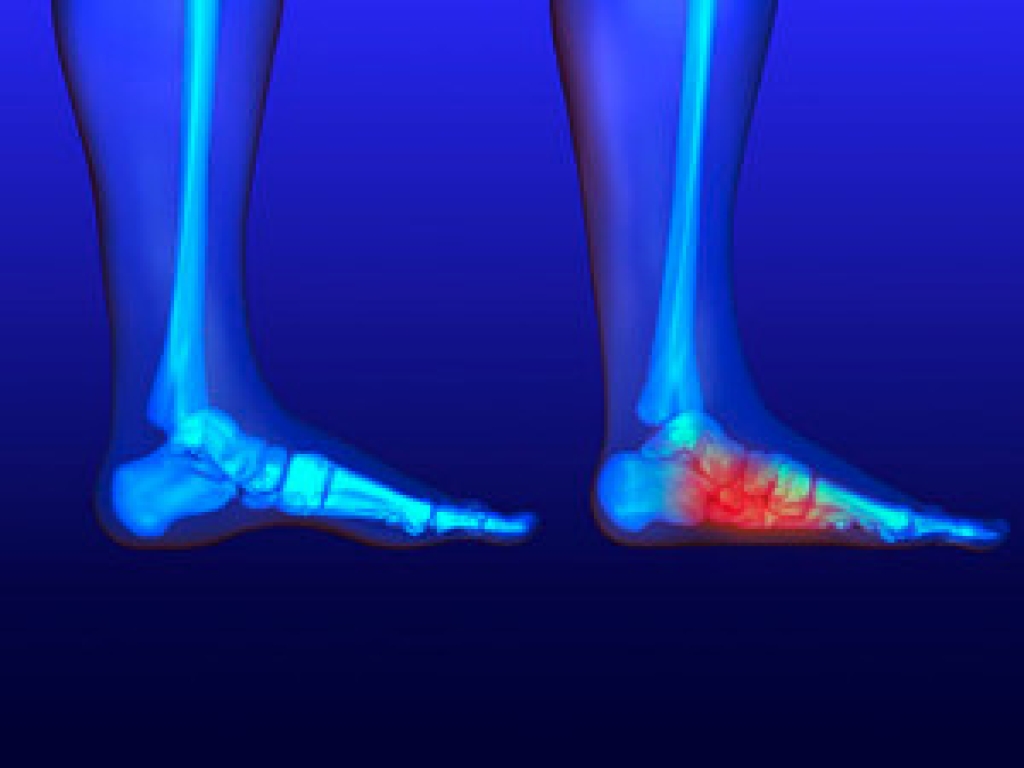

Sesamoiditis is a common condition among athletes in which inflammation occurs in the sesamoid bones in the feet. These bones, whose main function is to assist foot tendons in the movement of the big toe, can be injured either through athletic activity, such as dancing or running, or improper footwear like high heels. Symptoms include pain and inflammation, which can worsen with activities like walking. Diagnosis of sesamoiditis is conducted through bone scans or MRIs. The best way in which one can help manage sesamoiditis is by seeing a podiatrist, who may prescribe physical therapy, anti-inflammatory drugs, and rest to help the sesamoid bones to heal.

Sesamoiditis is a condition of the foot that affects the ball of the foot. It is more common in younger people than it is in older people. It can also occur with people who have begun a new exercise program, since their bodies are adjusting to the new physical regimen. Pain may also be caused by the inflammation of tendons surrounding the bones. It is important to seek treatment in its early stages because if you ignore the pain, this condition can lead to more serious problems such as severe irritation and bone fractures.